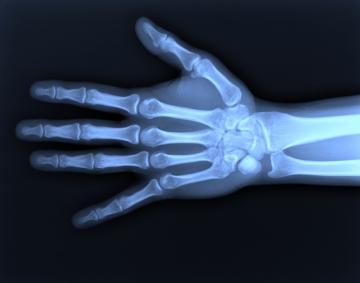

A través de una radiografía se obtiene la imagen de una parte del cuerpo y de los órganos internos que la componen. La parte a radiografiar recibe una mínima cantidad de radiación que se reflejará en una placa fotográfica. Esta radiación penetra con mayor o menor intensidad según el tipo de tejido u órgano de que se trate, identificando tanto pulmones, corazón o riñones como huesos o tumores. El paciente se coloca entre la fuente de radiación y la placa fotográfica. Se trata de una prueba segura y eficaz, tiene un uso diagnóstico previo a la realización de cualquier tratamiento Leer más sobre el artículo "Radiografías en el embarazo"